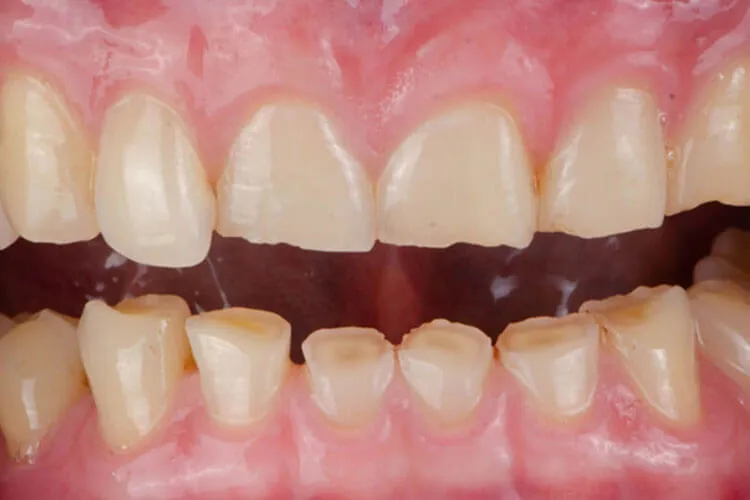

Occlusal trauma – The abnormal wear patterns on the occlusal surfaces can lead to fractures in the teeth.

Myofascial pain – The grinding associated with bruxism can eventually shorten and blunt the teeth. This can lead to muscle pain in the myofascial region and headaches.